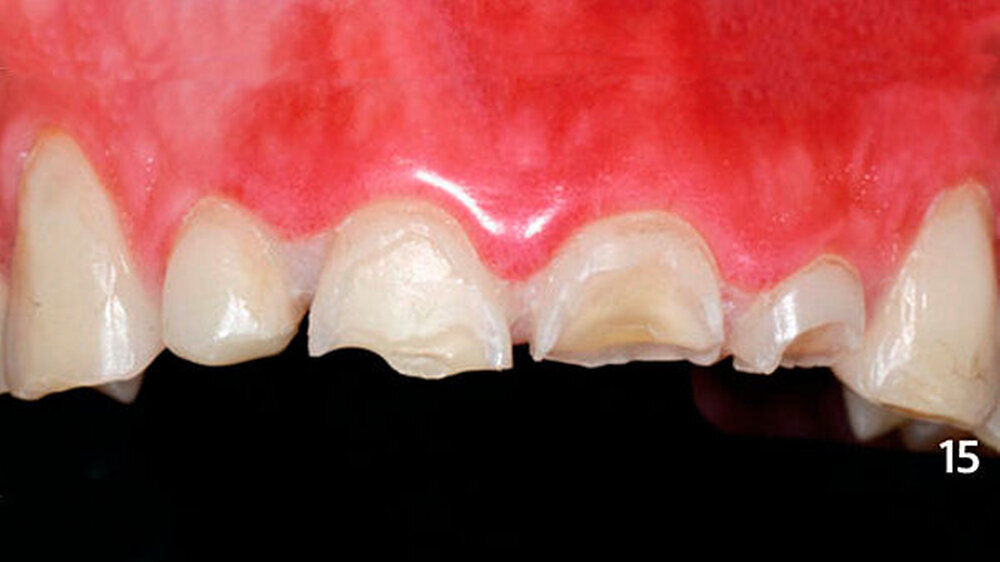

Nach der Bisshebung im Unterkiefer wurden die erosiven Frontzahndefekte im Oberkiefer ebenfalls mit Kompositadhäsiv versorgt (Abb. 14). Zunächst wurden die bukkalen Zahnhartsubstanzverluste freihändig mit Komposit aufgebaut (Abb. 15), und es wurde eine Alginatabformung genommen. Im zahntechnischen Labor wurden die inzisalen Anteile der Zähne aufgewachst, sodass anschließend ein Silikonschlüssel angefertigt werden konnte (Abb. 16).